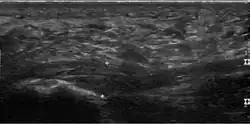

Im Falle einer Plantarfasziitis zeigt die Ultraschalluntersuchung (Sonografie) eine Verdickung der Aponeurosis plantaris. Die Aponeurosis ist am Ansatz am Fersenbein entweder mindestens 4,0 mm dick oder 0,6 mm dicker als am anderen Fuß.[2] Auch diffuse hypoechogene (im Ultraschall dunkel dargestellte) Flächen werden gesehen, die als Wassereinlagerungen (Ödeme) aufgrund von kleinsten Rissen interpretiert werden.[10] Bei etwa 40 Prozent aller Patienten wird eine erhöhte Durchblutung (Hyperämie) festgestellt, was auf einen akuten Verlauf hinweist. Bei einem chronischen Verlauf wird Hyperämie nicht festgestellt.[10] Die Dicke der Aponeurosis plantaris verringert sich bei erfolgreicher Behandlung, weswegen sie als objektives Maß verwendet werden kann.[2]